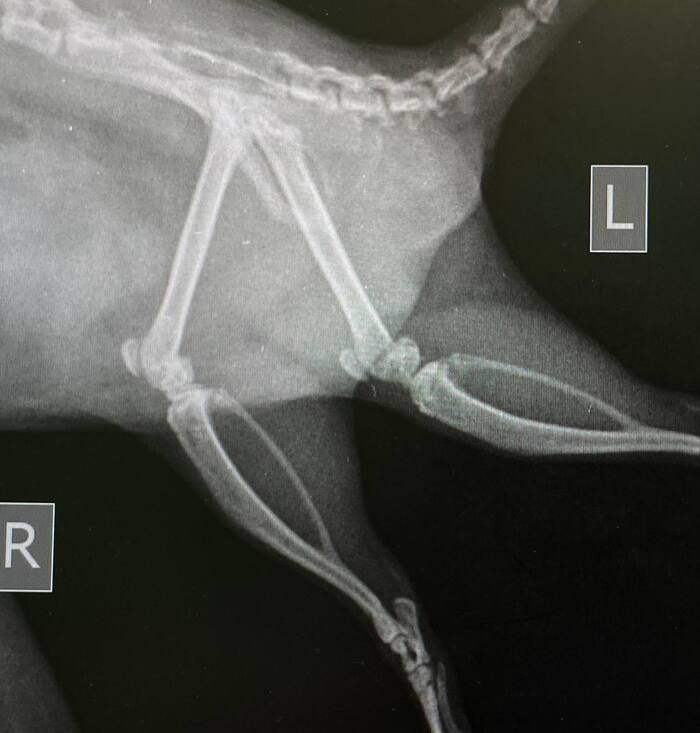

По осмотру и пальпации я устанавливаю болезненность в коленном суставе. Идем делать рентген.

Ничего критичного, обычные старческие артриты/артрозы начинаются.